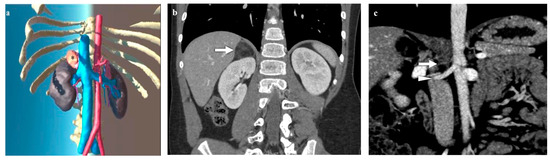

3.3. Kidney Lesions and Congenital Anomalies